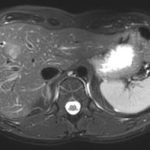

L’IRM abdominale est d’une grande utilité lorsqu’une analyse très fine des organes situés au sein de la cavité abdominale est nécessaire et que certaines lésions ne sont pas visibles avec les autres techniques d’imagerie (radiographie, échographie ou scanner).

Elle permet de réaliser des images en coupe ou acquisitions 3D apportant non seulement des informations sur l’anatomie de l’organe mais également sur la viabilité de certaines lésions et d’évaluer ainsi la réponse au traitement de façon plus précise.

Ce type d’exploration s’intéresse au foie, aux surrénales, aux reins, au pancréas, à la rate et au péritoine